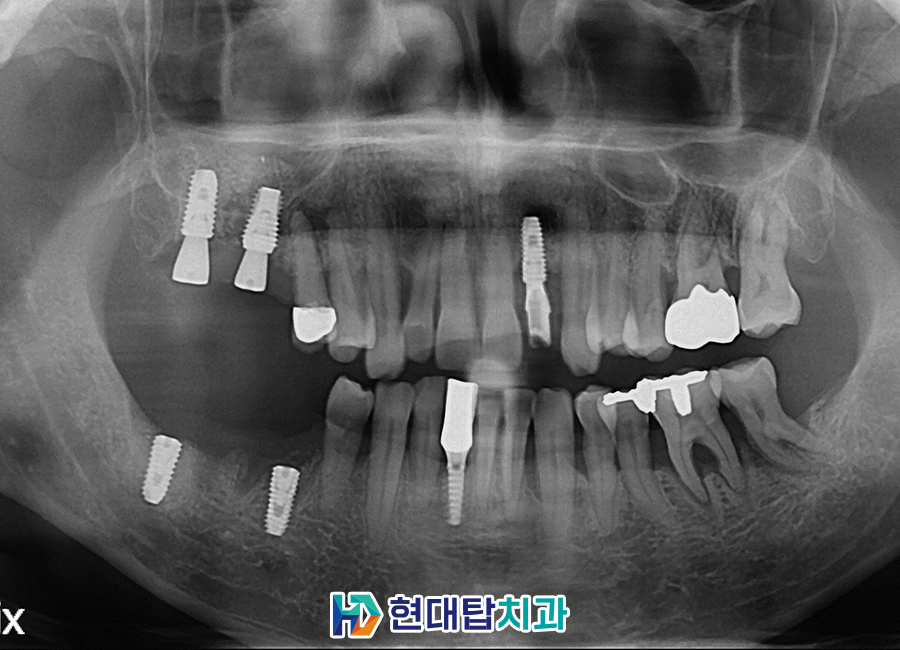

전반적으로 만성 치주염이 오랜 기간

지속되어 오신 상태로 잇몸뼈가

녹아있는 부분이 많이 관찰되었습니다.

또한, 오른쪽 위, 아래 모든 어금니 부위

예후가 불량한 상태였고, 왼쪽 앞니도

염증으로 인해 흔들림이 있는 상태였으므로

살려서 쓰기 힘든 치아들을

발치한 후 임플란트를

수면으로 진행하시기로 하였습니다.

기존 오른쪽 아래 임플란트 또한

임플란트 주위염으로 인해 제거가

불가피한 상황이었습니다.